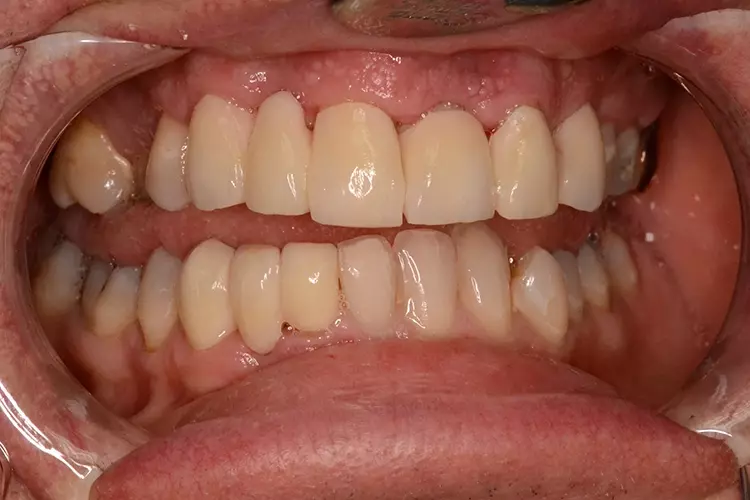

Bei dem heute 49-jährigen Patienten wurde seit Kindertagen versäumt, die Ober- und Unterkieferzahnbögen kieferorthopädisch auszurichten. Der Patient leidet seitdem stark unter seinen Zahnfehlstellungen.

Die Fraktur des stark elongierten Zahnes 21 war für den Patienten der Ausgangspunkt, sowohl die Front des Ober- als auch des Unterkiefers prothetisch überarbeiten zu lassen. Dabei wurde der frakturierte Zahn 21 durch ein navigiert eingesetztes Sofortimplantat ersetzt, während die verschachtelt stehenden Zähne 12 und 42 durch eine Brückenversorgung korrigiert wurden (Abb. 4a-j).